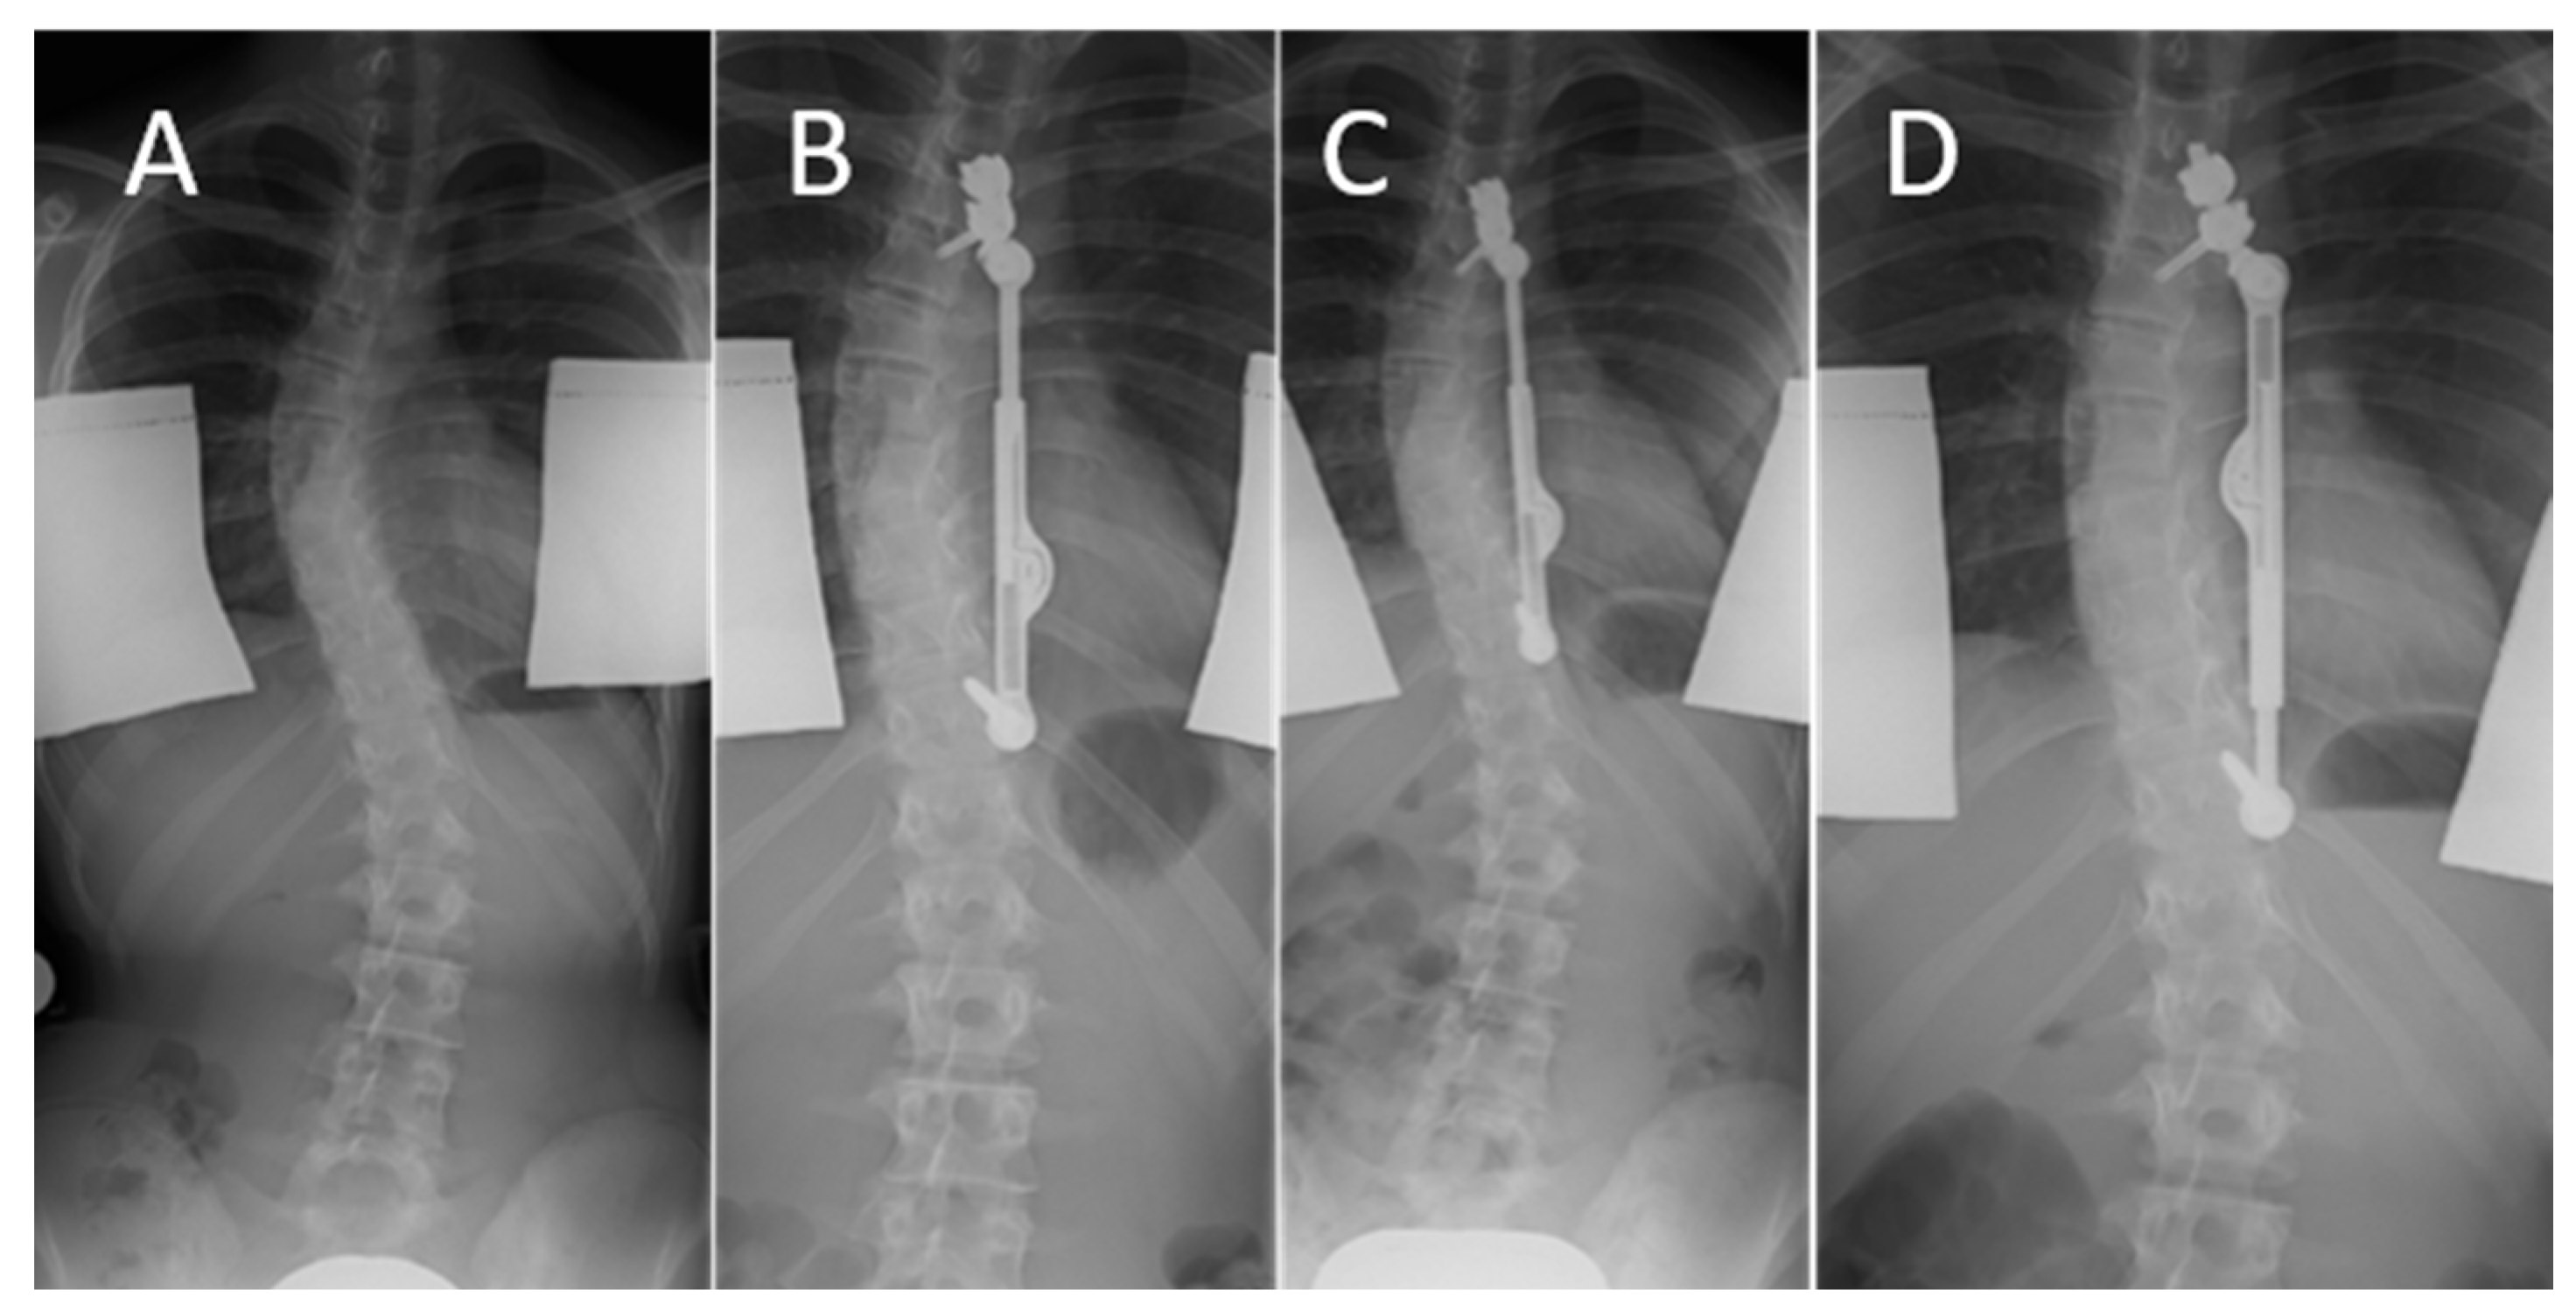

- Trobisch, P.D.; Kobbe, P.; Baroncini, A. Dynamic Scoliosis Correction as Alternative Treatment for Patients with Adolescent Idiopathic Scoliosis: A Non-Fusion Surgical Technique. Z. Orthop. Unfall. 2020, 158, 641–646. [Google Scholar] [CrossRef]

- Floman, Y.; Burnei, G.; Gavriliu, S.; Anekstein, Y.; Straticiuc, S.; Tunyogi-Csapo, M.; Mirovsky, Y.; Zarzycki, D.; Potaczek, T.; Arnin, U. Surgical management of moderate adolescent idiopathic scoliosis with ApiFix®: A short peri- apical fixation followed by post-operative curve reduction with exercises. Scoliosis 2015, 10, 4. [Google Scholar] [CrossRef] [PubMed]

- Floman, Y.; El-Hawary, R.; Lonner, B.S.; Betz, R.R.; Arnin, U. Vertebral growth modulation by posterior dynamic deformity correction device in skeletally immature patients with moderate adolescent idiopathic scoliosis. Spine Deform. 2021, 9, 149–153. [Google Scholar] [CrossRef] [PubMed]